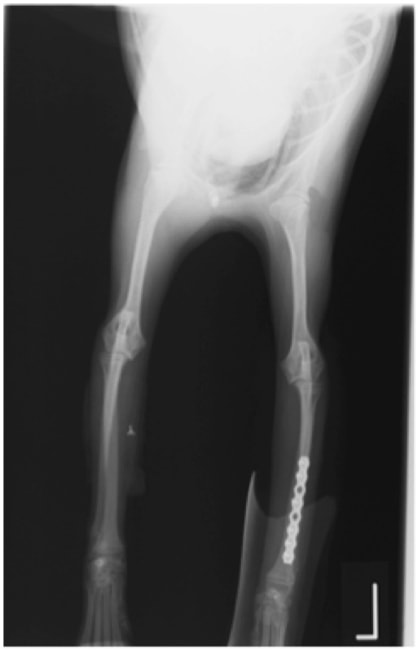

症例3:キルシュナーワイヤーのピンニングによる整復

ペルシャ猫 11ヶ月齢 雄

他院にて左大腿骨遠位の成長板骨折(salter-harrisⅠ型)が認められており、治療相談を目的として来院。当院にて、キルシュナーワイヤーを用いたピンニングにより骨折部位の整復を行いました。術後の経過は良好で、現在も経過観察中です。

術前レントゲン

術後レントゲン

Arthrex社のターゲティングデバイスを用いてピンニングの位置を調整することで、確実な固定を行っています。当院ではこの手術器具以外にも、人の手術にも使用される様々な器具を導入し、手術精度を高め、また医療メーカーと新しい器具の開発、試作にも取り組んでおります。